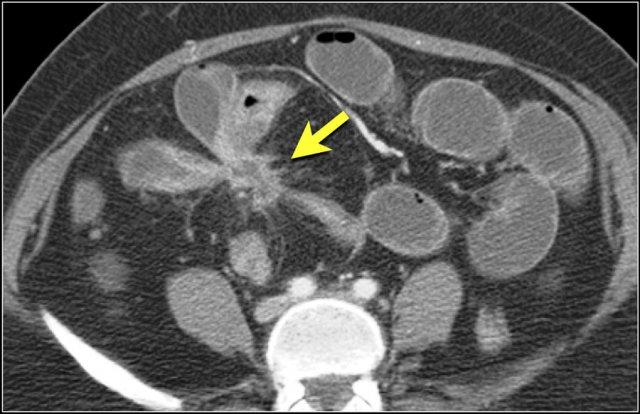

Đây là hình ảnh bệnh nhân thiếu máu cục bộ ruột do huyết khối tĩnh mạch mạc treo tràng trên – SMV (mũi tên đỏ).

Lưu ý tình trạng ứ máu tĩnh mạch trong mạc treo ruột (mũi tên vàng).